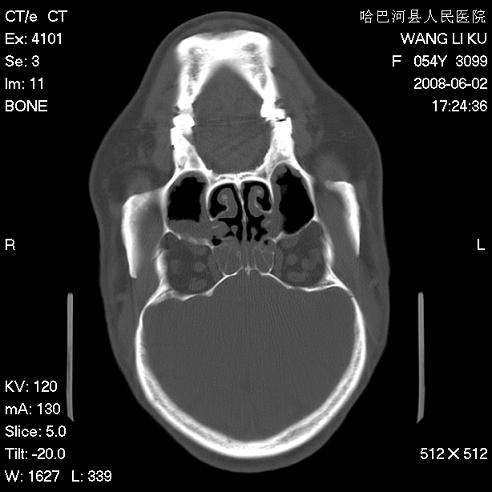

标题: CT13803:反复性鼻塞、流涕一年余 [打印本页]

标题: CT13803:反复性鼻塞、流涕一年余

副鼻窦炎,右上额窦积脓。左眼肌锥内见致密影,视神經受压

1.全组副鼻窦炎2.双侧上颌窦积液

1)全副鼻窦炎(左侧上颌窦黏膜下囊肿或息肉)。2)左眼眶肌锥内不规则小结节状软组织密度影;考虑为小血管瘤可能。建议行ct增强扫描检查。

全组副鼻窦炎,左侧肌锥内不规则形软组织肿块影,与眼外肌密度相当,左侧视神经受压,肿块与视神经及眼外肌分界清晰,眼外肌无增粗,眶壁无破坏,球后脂肪间隙不模糊,考虑良性改变,小血管瘤或神经源性肿瘤可能,建议增强扫描。

谢谢,增强扫描做了,眶内病灶与海绵窦同步明显强化,血管瘤